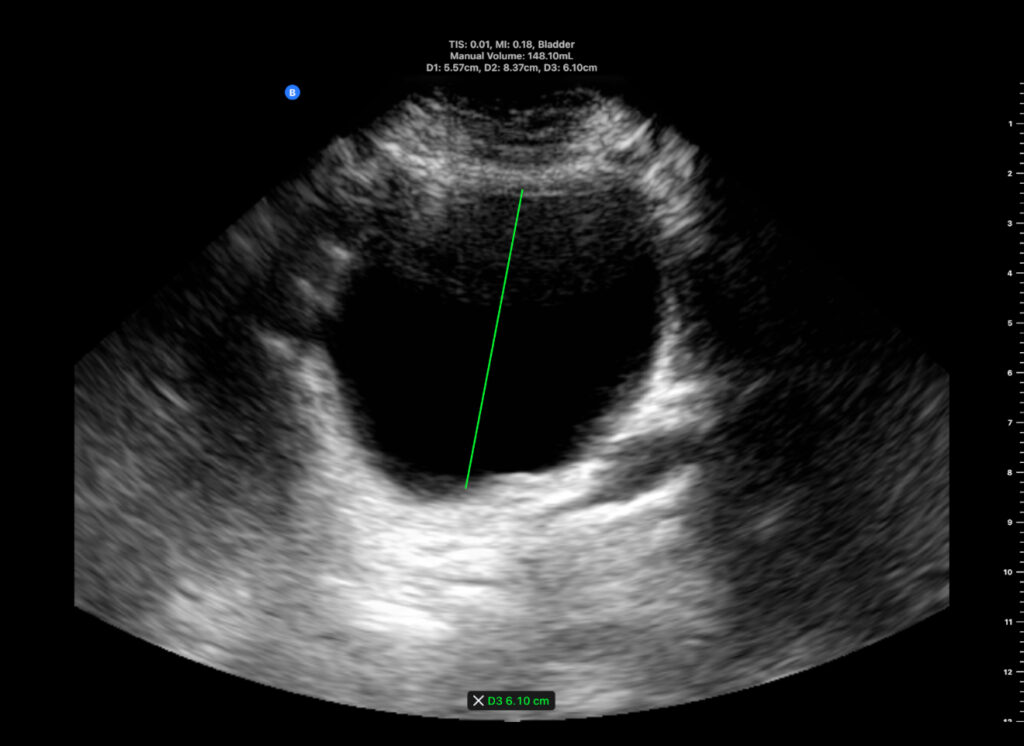

A 78-year-old male. Degenerative Parkinsonism. Bladder US, pre-void volume = 148 ml.